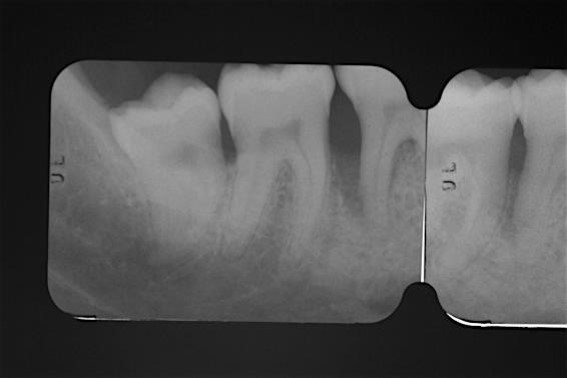

03/22 - Pre-operative radiograph. Deep intrabony defect visible on the distal aspect of tooth 46.

Deep intrabony defects treated using Straumann® Emdogain® - Dr. M. Stefanini

04/22 - Pre-operative radiograph. Deep intrabony defect visible mesially to tooth 45.